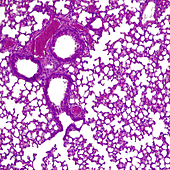

Iniciar sesiónLa predicción de la trombosis en pacientes con cáncer es un factor decisivo para mejorar su calidad de vida. La obstrucción de los vasos sanguíneos es una complicación frecuente en personas que reciben tratamientos como la quimioterapia o la radioterapia, que afectan directamente a ... la coagulación de la sangre.

Un equipo del Instituto de Investigación Biomédica del Hospital Sant Pau de Barcelona, en colaboración con el Hospital General Universitario Gregorio Marañón, de Madrid, ha desarrollado una herramienta que combina datos clínicos y genómicos del paciente para predecir su riesgo de sufrir esta clase de eventos y mejorar así su estancia en el hospital.

Este nuevo equipo de diagnóstico, llamado Oncothromb, aplica por primera vez un algoritmo basado en el análisis de variantes genéticas de factores de coagulación y los combina con tres índices de riesgo clínico clásicos: tipo de tumor, estado de la enfermedad e índice de masa corporal. También permite identificar a los pacientes con un nivel de riesgo alto, moderado o bajo, y actuar en consecuencia.